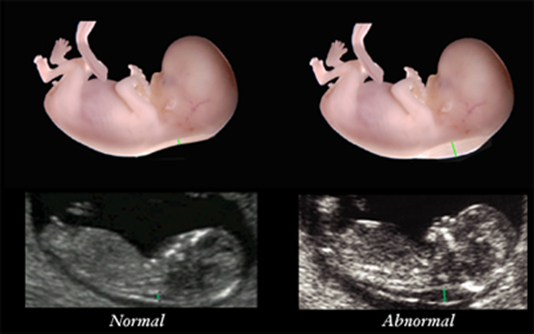

Bebeğin kafatasında yer alan basınç artışı kemiklerin baskıya uğramasına birbirinden ayrılmasına ve kafanın olması gerekenden büyük görünmesine neden olabilir.

Hamilelikte bir çok kadının yaşadığı üzüme hissinin sebeplerini nedenlerini sizler için detaylıca araştırdık. Hidrosefali beynin odacıklarında bulunun sıvı miktarının artması sonucunda kafa içindeki basıncın yükselmesi ve beynin zarar görmesidir. Yetişkinlerde ve çocuklarda gelişen hidrosefali genellikle beyni etkileyen bir hastalık veya yaralanmadan kaynaklanır. Beyin suyunun devir daim ettiği yulaklarda tıkanıklık darlık ya da açılmamaya bağlı tam kapalılık çocuklardaki hidrosefalinin en sık karşılaşılan sebeplerindendir.

Bebeklerde hidrosefali durumu kafatasının genişlemesine ve kafatasında çıkıntı oluşmasına neden olabilmektedir. Bu nedenle hamilelik sırasında aktif kalmak için bir neden daha var. Hamilelikte ayak şişliği neden olur.